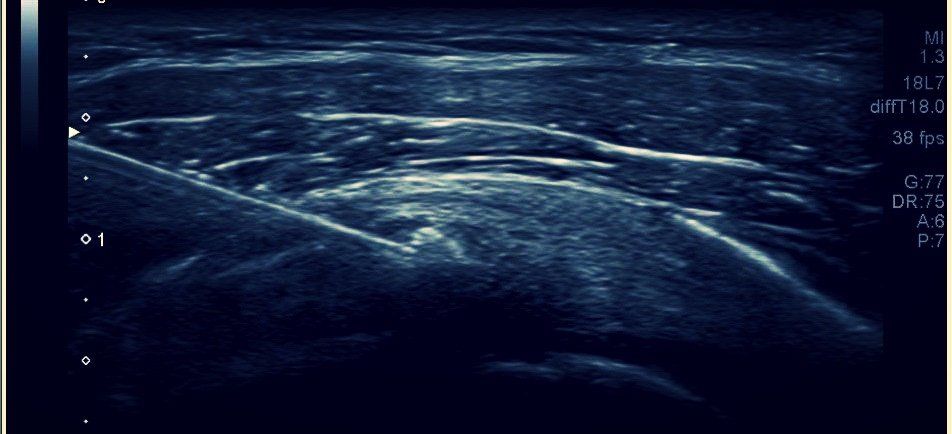

Ces infiltrations sont réalisées avec matériel stérile et sous contrôle échographique complet afin de s'assurer du lieu de l'infiltration et de ne pas léser les structures anatomiques adjacentes.

-Les ponctions infiltrations échoguidées de corticoïdes en cas de ténosynovite ou de bursite.

-La ponction trituration échoguidée en cas de volumineuse tendinopathie calcifiante.

-Le criblage tendineux échoguidé et/ou les PRP (plasma riche en plaquettes) en cas de tendinopathie fissuraire sans évolution favorable.